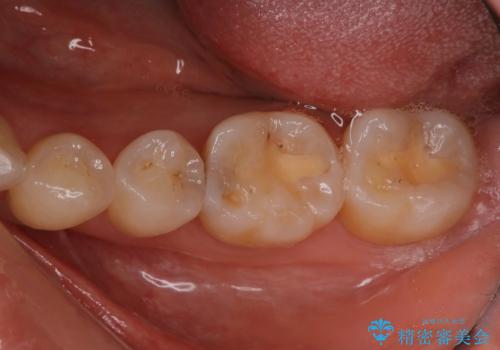

定期検診で虫歯発見。セラミック治療

- 定期検診に通われている患者様で虫歯を発見し患者様に話をしたら、治療を進めていきたいとのことだったので治療を行いました。

まずは虫歯をしっかりと取る事が大切です。

虫歯をとった後は、削った形に型を取る事で隙間なく歯にあった被せ物ができてきます。